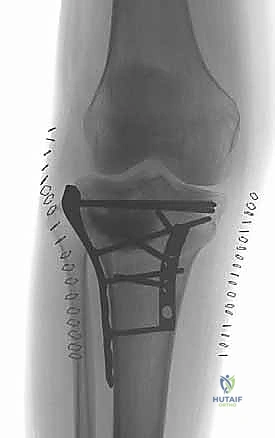

To effectively communicate and formulate operative strategies, a rigorous application of classification systems is mandatory. The Schatzker classification remains the most universally utilized framework in clinical practice. Within this system, bicondylar injuries are categorized as Types V and VI. A Schatzker Type V fracture denotes a bicondylar injury where the medial and lateral articular segments are fractured, but crucially, there remains a continuity between the articular block and the tibial diaphysis. These fractures, while severe, often preserve a central pillar of intact bone, which can be leveraged during reduction.

In stark contrast, the Schatzker Type VI fracture is defined by complete metaphyseal-diaphyseal dissociation. In this catastrophic injury, the entire articular block is completely severed from the tibial shaft, effectively rendering the knee joint floating. This pattern implies a significantly higher energy transfer, massive soft tissue stripping, and profound instability. The surgical approach to a Type VI injury is inherently more complex, often requiring extensive dual plating to bridge the metaphyseal-diaphyseal defect and restore the mechanical axis.

While the Schatzker system is invaluable, the AO/OTA classification provides a more granular, alphanumeric categorization that is essential for academic research and precise surgical auditing. Bicondylar fractures fall under the 41-C category (complete articular fractures). These are further subdivided into C1 (articular simple, metaphyseal simple), C2 (articular simple, metaphyseal multifragmentary), and C3 (articular multifragmentary). The C3 variant, representing the most complex morphology with extreme articular comminution, tests the limits of surgical reconstruction. Furthermore, modern CT-based classifications, such as the Luo three-column concept, have revolutionized our understanding by dividing the plateau into medial, lateral, and posterior columns. This three-dimensional conceptualization is critical, as it mandates that each fractured column must be independently addressed and stabilized to prevent multi-planar collapse.

The restoration of the native angular relationships of the proximal tibia is non-negotiable. The medial proximal tibial angle (MPTA), typically measuring 87 degrees (range 85-90 degrees) relative to the anatomical axis of the tibia, dictates the coronal plane alignment. Failure to restore the MPTA results in mechanical axis deviation, leading to asymmetric joint loading and accelerated unicompartmental arthrosis. Equally critical is the proximal posterior tibial angle (PPTA), which defines the posterior slope of the articular surface, averaging 81 degrees (range 77-84 degrees). This posterior slope is a fundamental determinant of knee kinematics, particularly sagittal plane stability and cruciate ligament tension. An iatrogenic alteration of the PPTA can result in profound anterior or posterior instability, severely compromising the functional outcome.